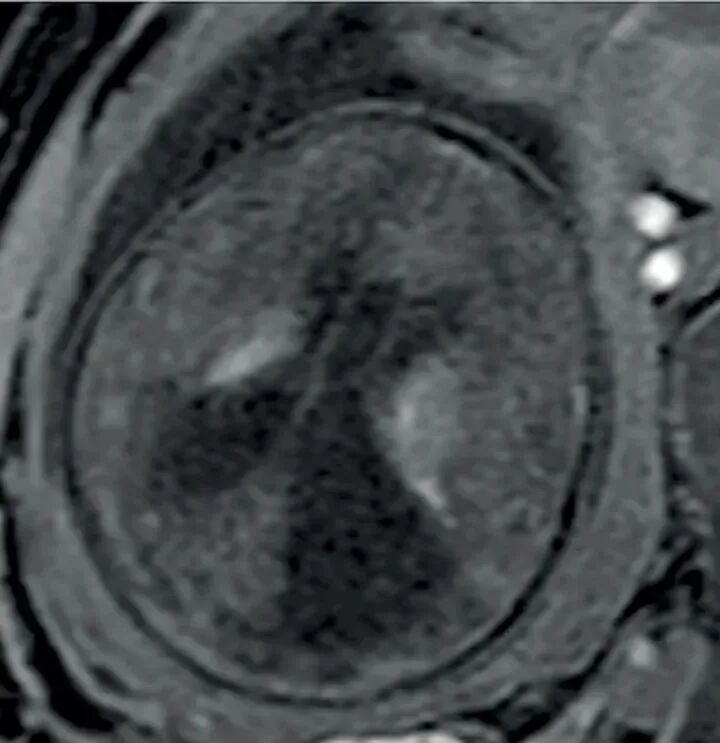

随后行MRI检查显示尾状核丘脑沟异常信号,脑室周围白质广泛水肿样改变(图3),胎儿大头畸形及肝脾大。